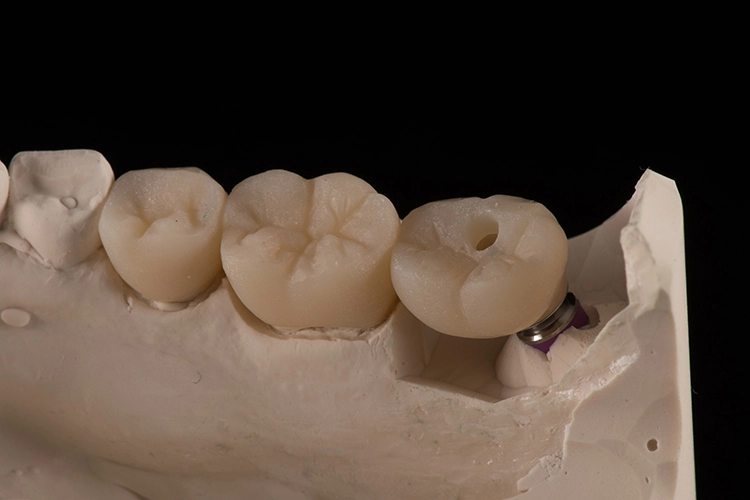

Bilder: Dr. Lampson / HannkerNach dem Ausgießen der Abformung sowie dem Scan des Gips- und Antagonistenmodells (Abb. 11a bis d) folgten das Kronendesign und die Fräsparametereinstellung per CAD/CAM-Programm (PowerMill Pro, Autodesk) (Abb. 12). Hergestellt wurden die Kronen aus Lithium-Disilikat-CAD/CAM-Blöcken (InitialTM LiSi Block, Farbe A2) (Abb. 13), die sich insbesondere durch eine hohe Opaleszenz bei hochtransluzenten (HT) Farbtönen auszeichnen und so auch ohne weitere Charakterisierung hochästhetische Ergebnisse erzielen.

Bilder: Dr. Lampson / HannkerNach 35-minütigem Schleifen (Exocad PowerMill CAM, DMG) wurde die Restauration aus dem Block entfernt und der Bereich der Anstiftung geglättet. Anschließend galt es, die Kronen auf den jeweiligen Formen und am Modell zu prüfen, wobei sich bereits eine perfekte Randpassung zeigte (Abb. 14 und 15). Danach erfolgte die Glaslötung der Implantatkrone auf das individuell angepasste Zirkonoxid-Abutment (Abb. 16).